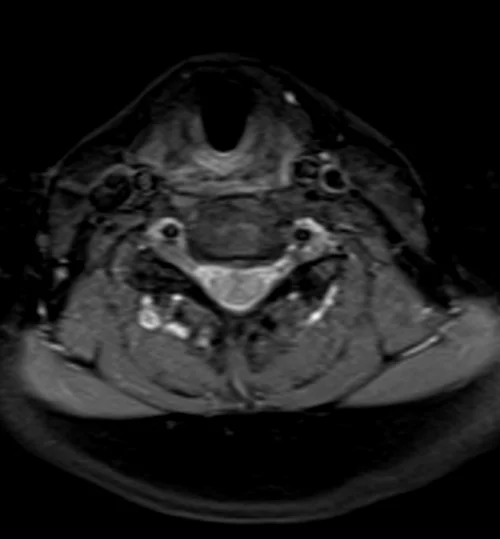

Neck MRA axial T1 fat sat images